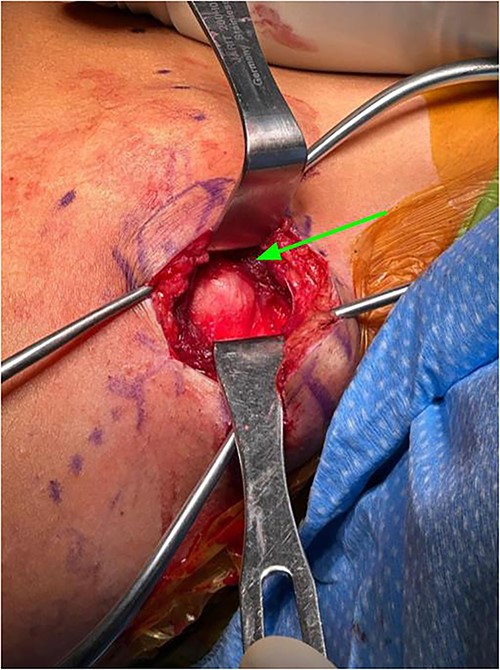

Subcutaneous tissue was divided with the electrocautery. Investing fascia over the trapezius was identified and the division between the superior and middle fibers of the trap was identified. The raphe between the superior and middle fibers was then bluntly spread in line (Fig. 3). We then encountered the superior aspect of the ventral lesion on the scapula (Fig. 4). Of note, the majority of levator scapulae fibers were medial to this lesion; however, the most lateral portion of the muscle was overlying the lesion. These lateral fibers were spread in line to expose the pedunculated mass. Blunt dissection was then taken circumferentially around the stalk of the mass to ensure all soft tissue had been freed from the area (Fig. 5). An osteotome was then carefully placed within the wound at the base of the stalk, and the tumor was then removed and sent to pathology for analysis. The stalk remnant was then filed down to a smooth and stable base with a rasp without any significant areas of potential irritation or prominence. The wound was then copiously irrigated with normal saline. Fluoroscopy images demonstrated complete resection of the bony tumor. There was no active bleeding within the wound. The fascia overlying the trapezius muscle and the skin were then closed.

Exposure after trapezius had been split between middle and superior fibers, levator scapula fibers can be seen medial to lesion (identified by arrow).